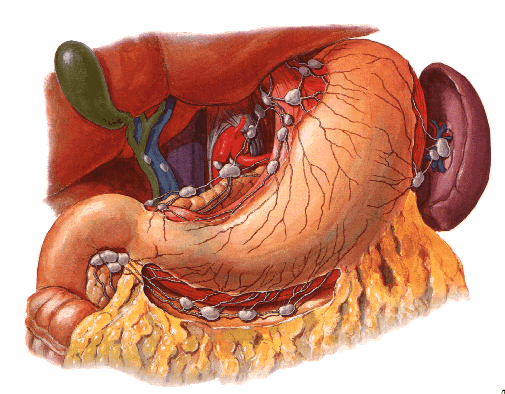

Drenagem linfática do estômago, canalículos linfáticos e linfonodos representados em branco. (associado à figura abaixo)